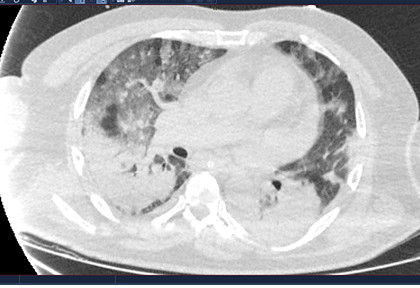

Routine clinical laboratory assays were performed in the hospital’s clinical laboratories. Clinical and laboratory information was extracted from the patients’ medical records. C reactive protein (CRP) in plasma was measured by immunoturbidimetry (Beckman Coulter, Krefeld, Germany). Interleukin-6 (IL-6) levels in plasma were measured by electrochemiluminescence (Siemens Medical Solutions Diagnostics, Siemens Healthcare, Erlangen, Germany). CT scans were read by experienced radiologists who scored results by severity using the criteria shown in Figure 1.

Figure 1. Clinical assessment of pneumonia severity based on computed tomography (CT) scores.

Scoring method: Mild (CT-1)—no more than three ground-glass opacities of <3 cm maximum diameter. Moderate (CT-2)—more than three ground-glass opacities; less than 50% involvement by visual assessment. Medium-heavy (CT-3)—ground-glass opacities and pulmonary consolidation; 50-70% involvement by visual assessment. Severe (CT-4)—diffuse ground-glass opacities with or without consolidation; more than 75% involvement by visual assessment.